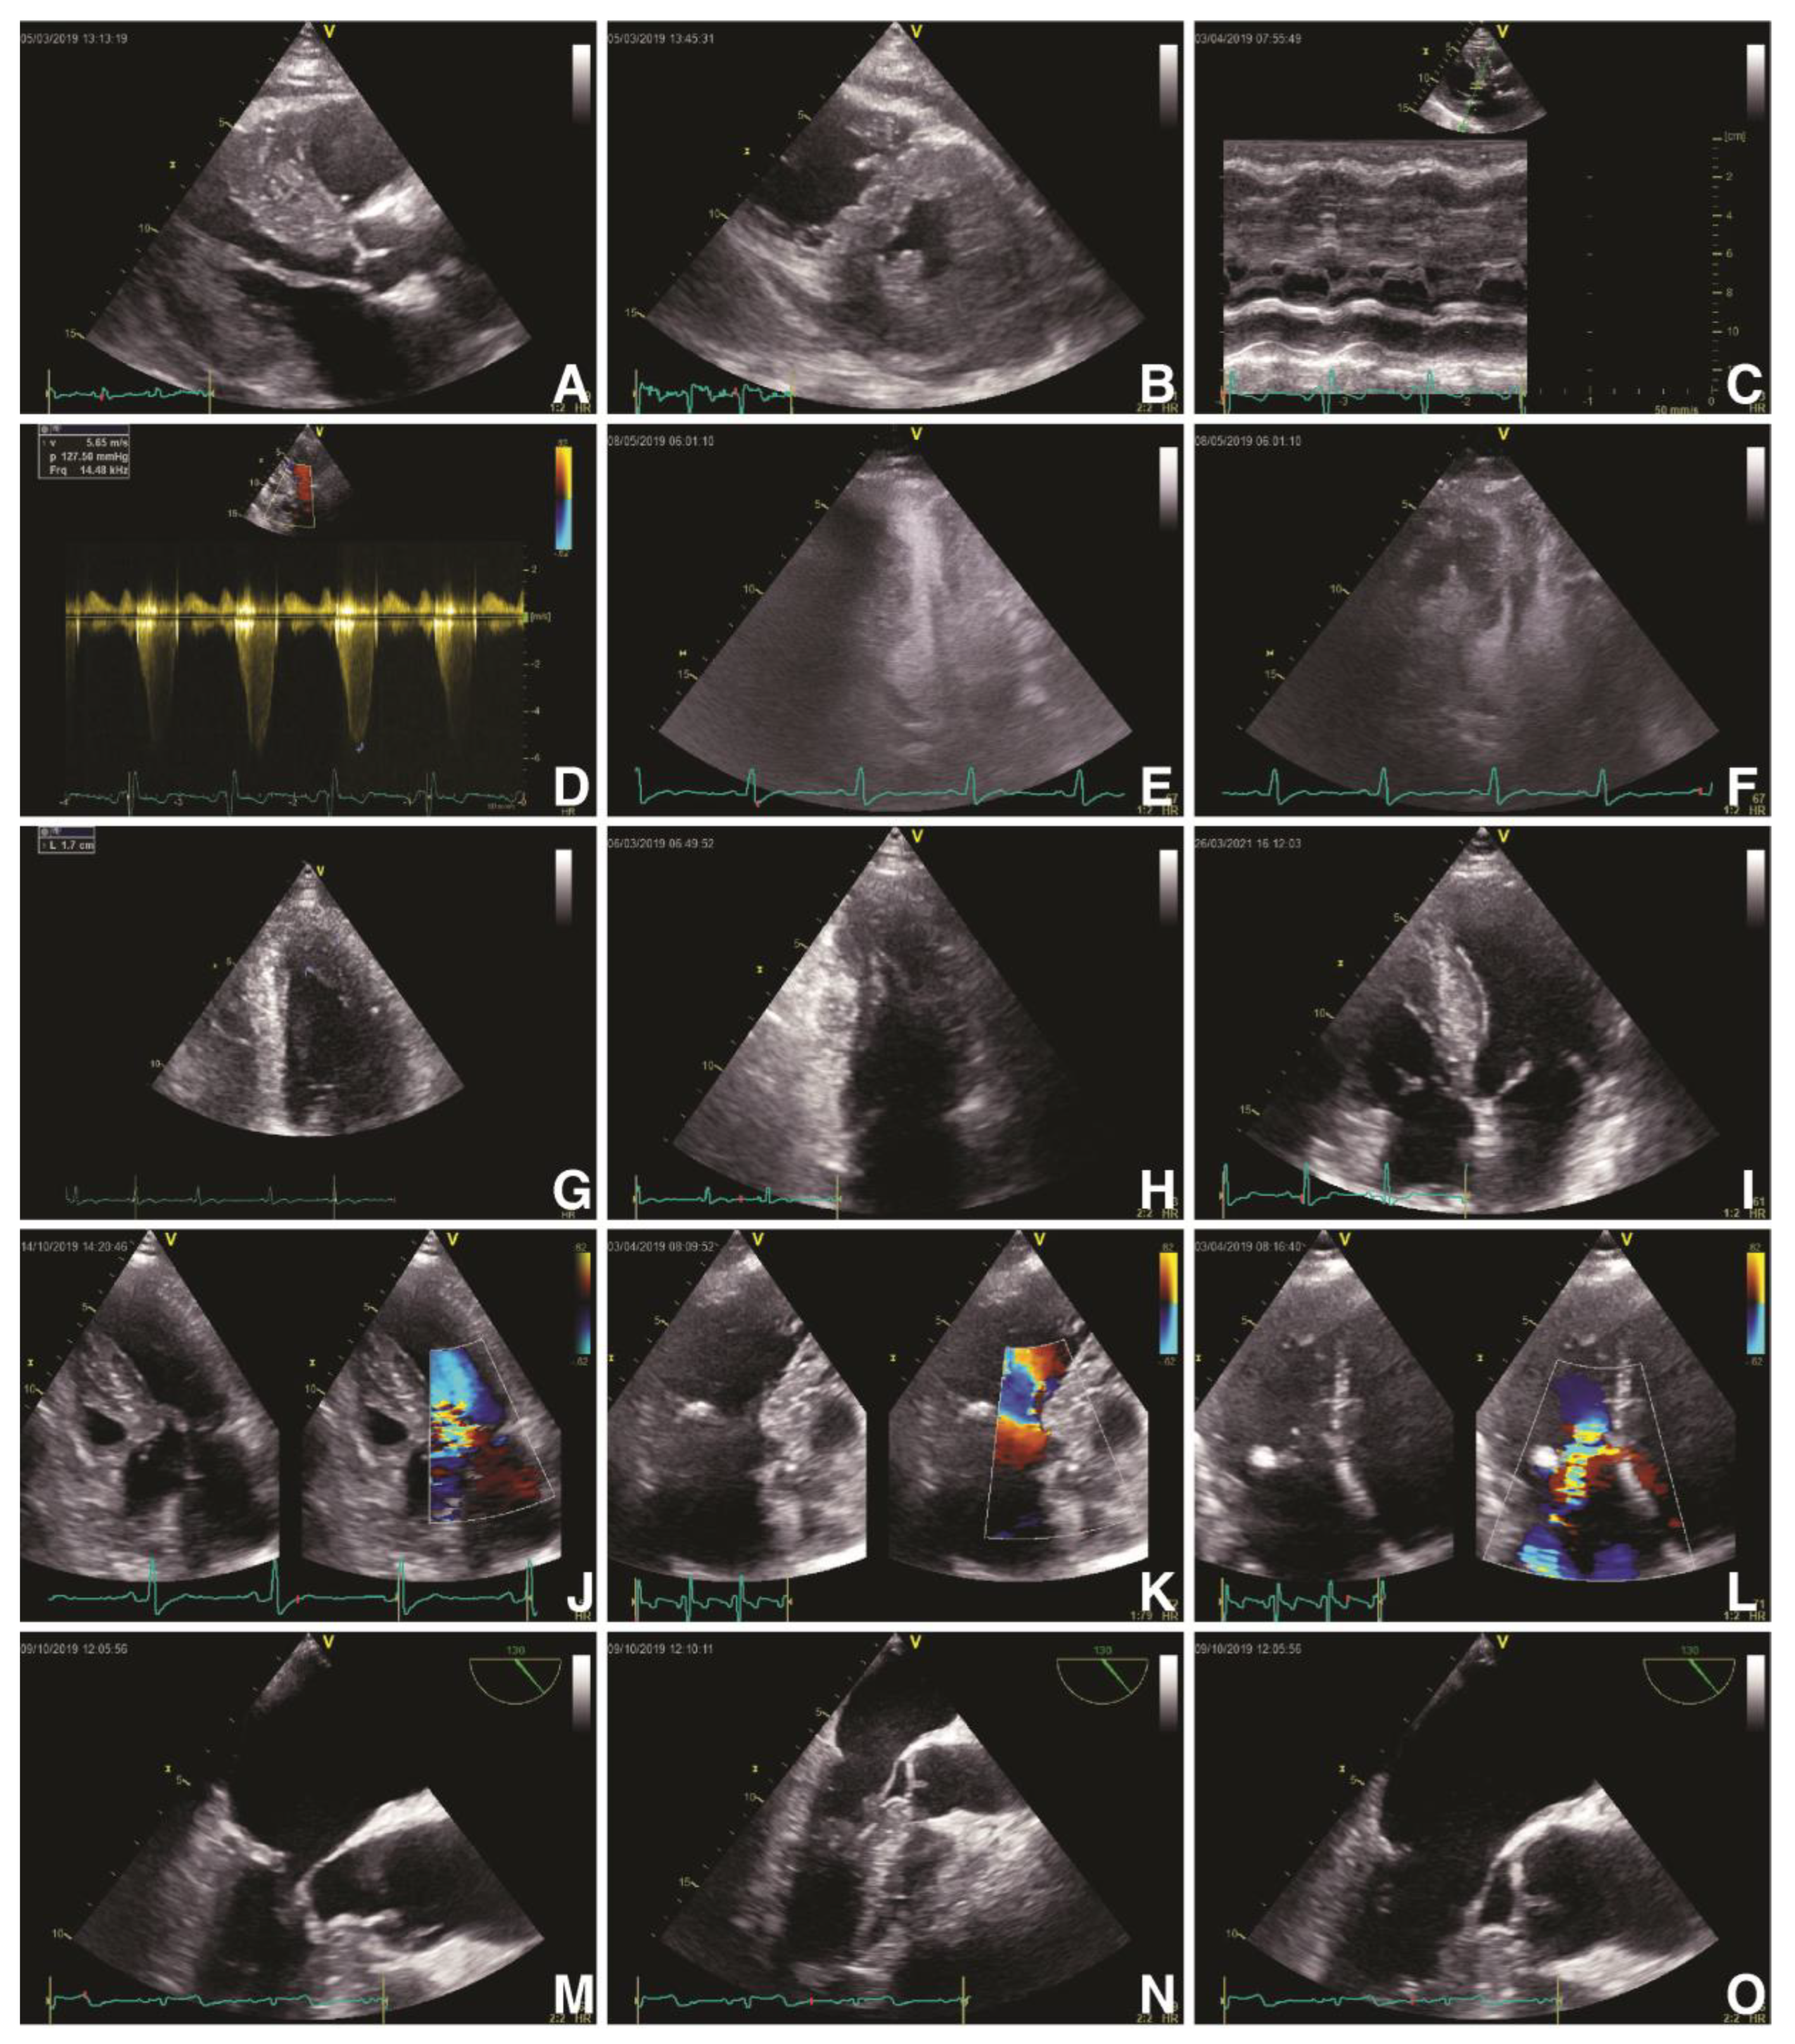

Current international guidelines recommend standard surface ECG with QRS duration measurement for establishing the indication of CRT, regardless of patients’ disease. Nevertheless, the major shortcoming in surface ECG is that it cannot accurately characterize various myocardial activation irregularities and it presents with a wide variety in defining LBBB, both leading to a significant number of patients who are CRT non-responders [9]. Additionally, the inhomogeneity in identifying and categorizing LBBB is caused by gaps in its proper definition, guidelines’ unevenness and intra- and inter-observer variability [52,53]. Hence, in a meta-analysis conducted by Cleland et al., which evaluated 3782 patients with proper recommendation for CRT, amongst QRS duration, LVEF and LBBB morphology, solely QRS interval was independently associated with all-cause mortality and hospitalization for HF [53]. Moreover, patients who exhibit NICD are also candidates for CRT, mainly based on their QRS duration; however, there is a considerable inconsistency in their response rate, especially due to the underlying myocardial illnesses [54]. More than that, in a study conducted by Kawata et al., which evaluated the impact of CRT in patients with NICD and right bundle branch block, only QRS duration of over 150 ms was associated with a positive response rate [55]. Thus, in patients with HCM, not solely the LBBB morphology should determine CRT, but rather the QRS duration should also be always taken into account. Various ECG morphologies can be found in Figure 5.

Figure 5. Clinical vignette of LBBB and post-CRT electrical patterns and post-procedural radiological anatomy in patients with hypertrophic cardiomyopathy treated with CRT (own collection of authors). (A)—typical LBBB activation; (B)—prior AAIR pacing for sinus node disease with atypical LBBB activation; (C)—atypical LBBB with apical aneurysm in midventricular hypertrophy pattern HCM; (D)—DDDR programming with LV-only pacing in optimal fusion intervals in an HCM patient with LBBB; (E)—DDD programming with biventricular pacing in an HCM patient; (F)—post-procedural radiological aspect of CRT-D device with mid-septal position of single-coil RV lead and posterolateral position of LV bipolar lead in a non-dilated hypokinetic HCM patient; (G)—post-procedural radiological aspect of a preexisting single-chamber ICD upgraded to CRT-D with a mid-septal position of dual-coil RV lead and posterolateral position of LV tetrapolar lead in a patient with end-stage dilated phenotype of HCM with severe LV dysfunction with newly developed LBBB; (H)—post-procedural radiological CRT aspect with mid-septal position of single-coil RV lead and posterolateral position tetrapolar multipoint LV lead in a patient with prior surgical septal myectomy. Abbreviations: LBBB, left bundle branch block; CRT, cardiac resynchronization therapy; HCM, hypertrophic cardiomyopathy; RV, right ventricle; LV, left ventricle.